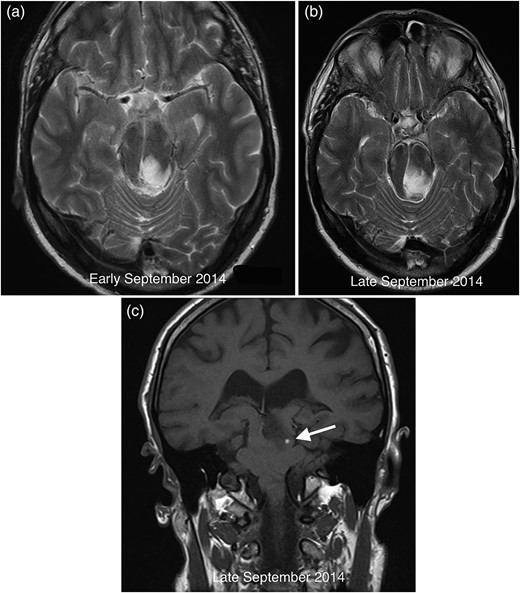

A third MRI performed in late September 2014 during an acute admission for worsening visual symptoms demonstrated interval enlargement of the midbrain mass (Fig. 2a and b) featuring acute petechial haemorrhage (Fig. 2c). There was no restricted diffusion or contrast enhancement at any time point. Sagging of the brainstem was evident on both studies in 2014, unchanged from the initial scan performed 2 years earlier.

Comparative axial T2 images demonstrating growth of the midbrain mass between early (a) and late (b) September 2014. The coronal T1 image from September 2014 (c) reveals petechial haemorrhage (arrow) in the lesion with corresponding susceptibility artefact on gradient echo imaging (not shown).